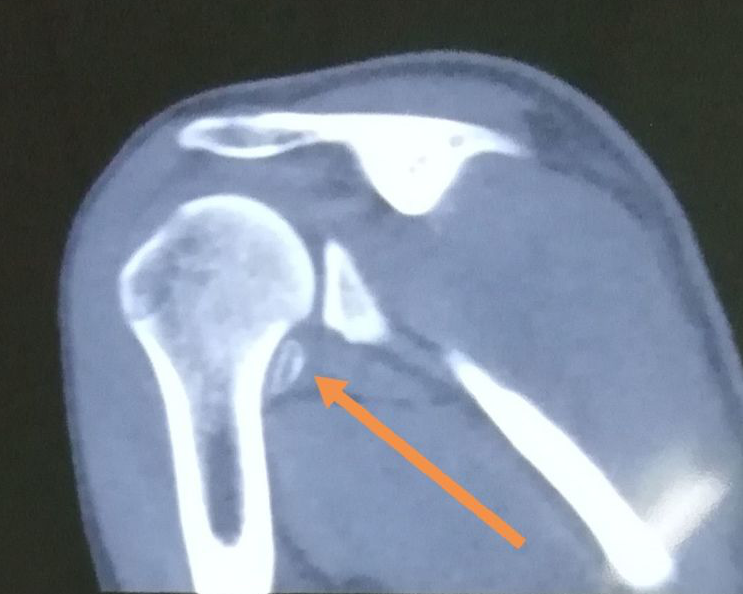

肩膀脱臼ct图片

肩膀脱臼ct图片,肩膀脱臼恢复锻炼图解

肩关节后脱位

复发性肩关节脱位